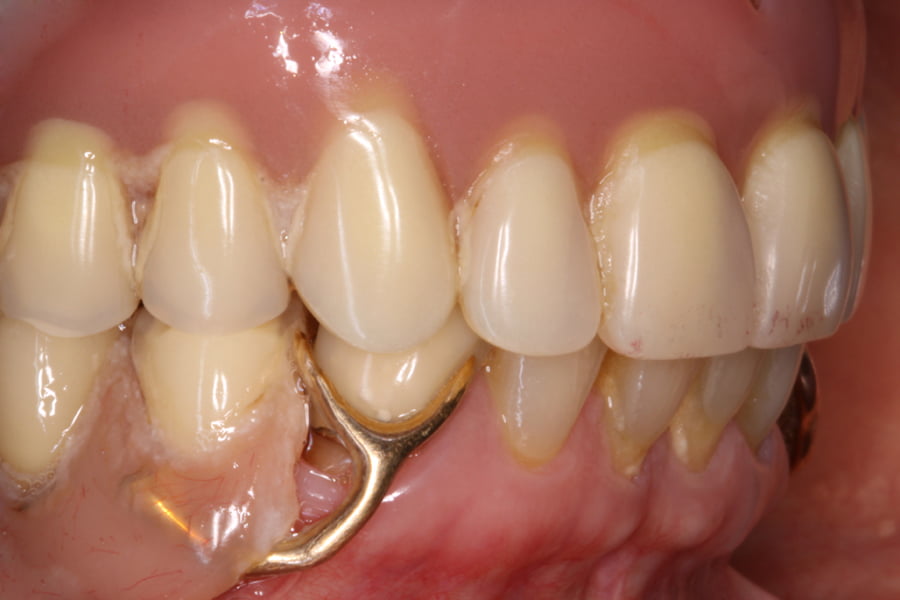

As seguintes imagens apresentam um dos casos incluídos no estudo (figura 03 – 15).